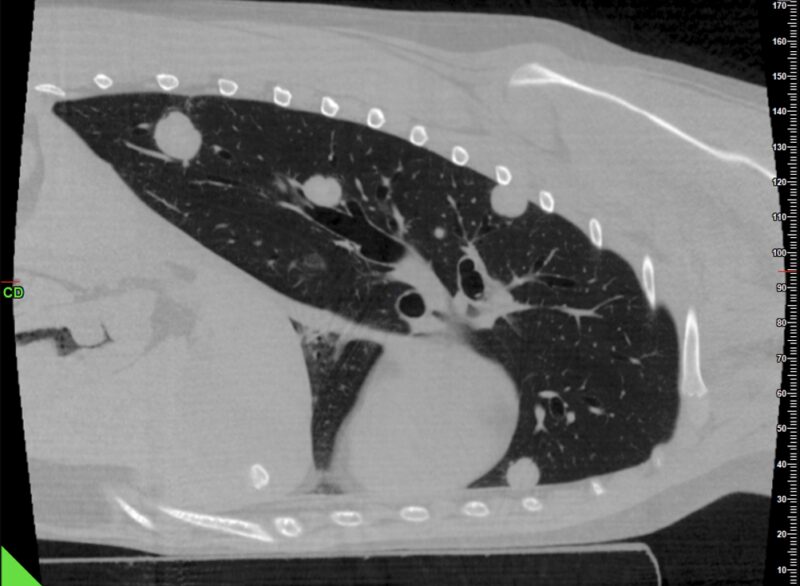

Thorax: Im Thorax wird das CBCT ebenso routinemäßig eingesetzt. Es erlaubt die Beurteilung von Raumforderungen, größeren parenchymatösen Veränderungen und mediastinalen Prozessen bei vergleichsweise kurzer Untersuchungszeit (Abb. 3 & 4).